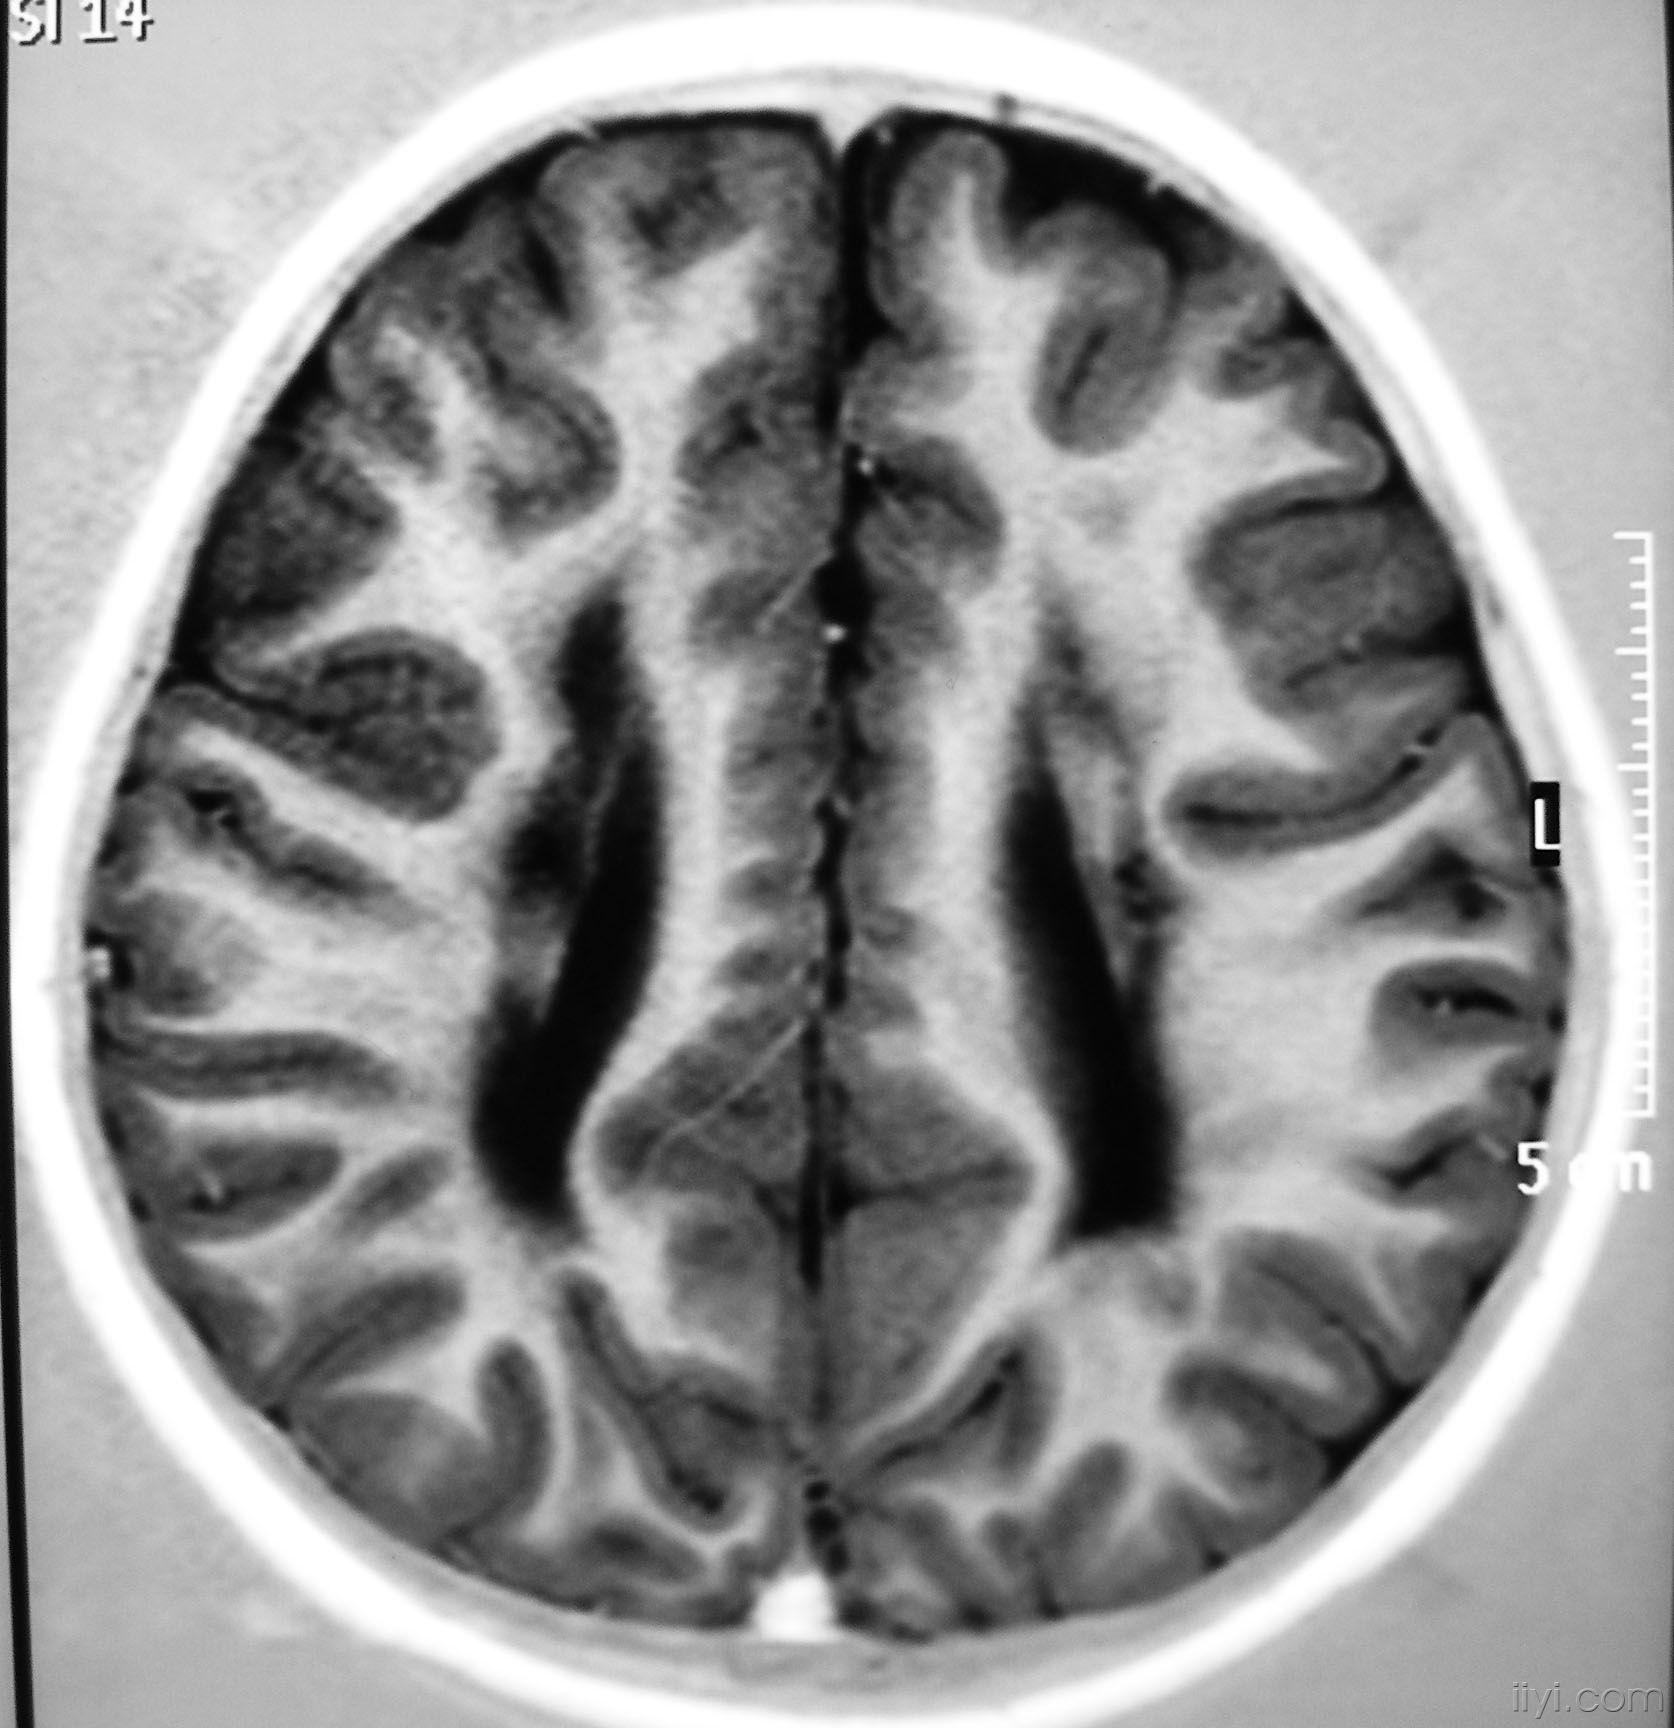

pvL

主要与脑缺血缺氧有关,多见于早产儿,是造成脑瘫的主要原因

影像学发生于侧脑室周围,侧脑室扩大,脑白质减少。扩大的侧脑室外缘常不规则为其特点,多为双侧脑室同时扩大。脑白质减少,脑皮层与脑室侧缘相近。MRI T1呈低信号,T2呈高信号。